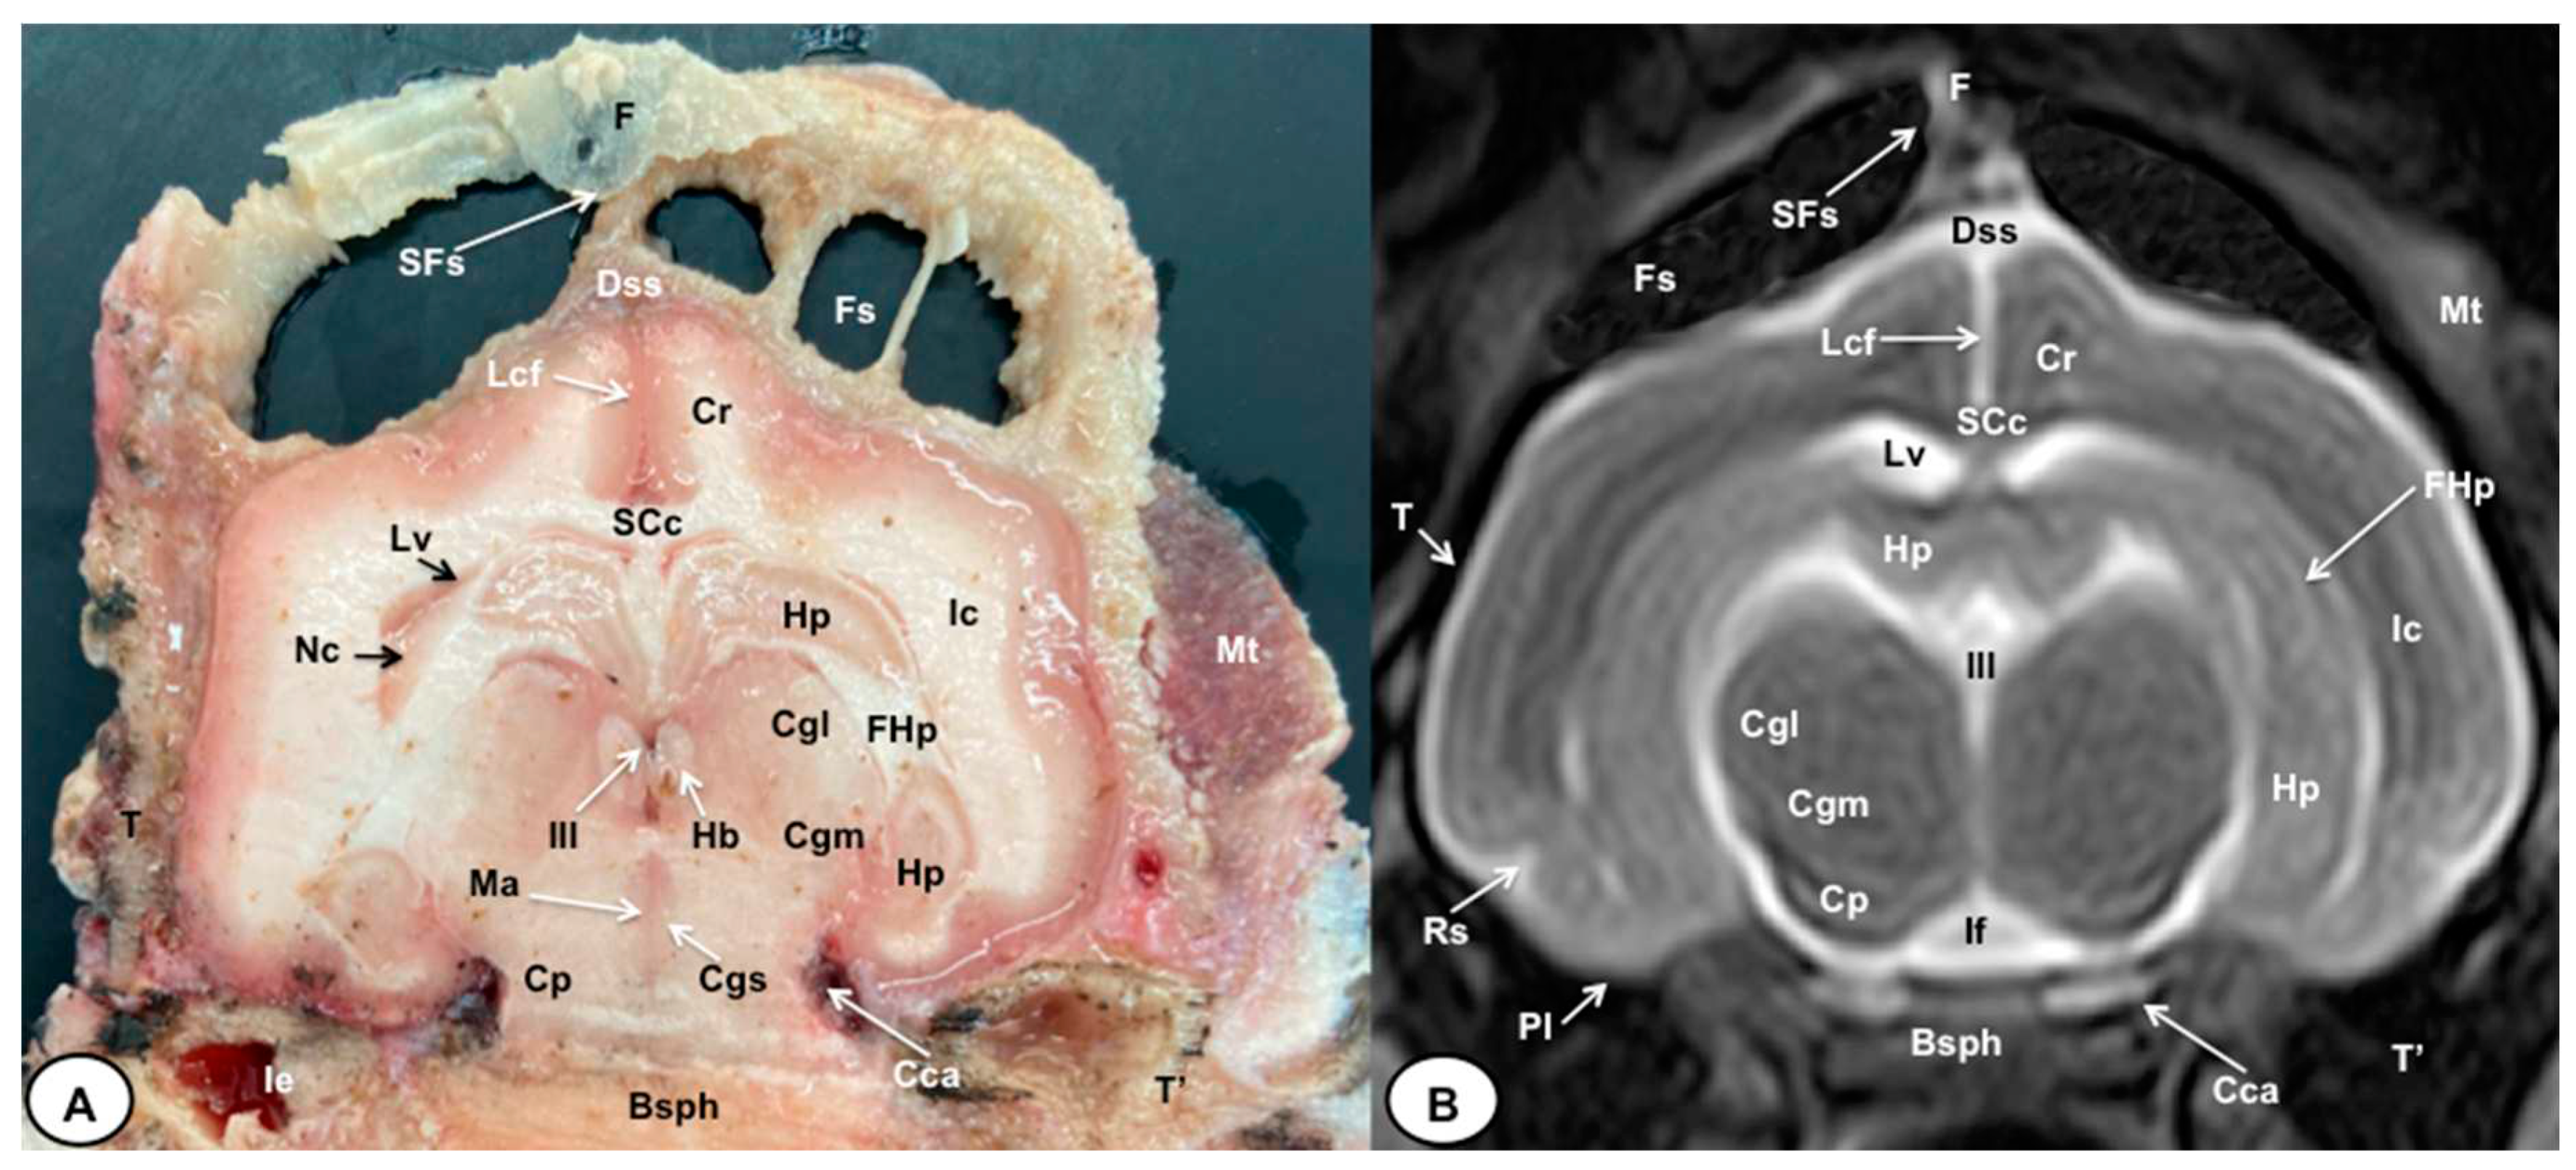

3.1. Anatomical gross-sections

3.2. Magnetic Resonance Imaging (MRI)